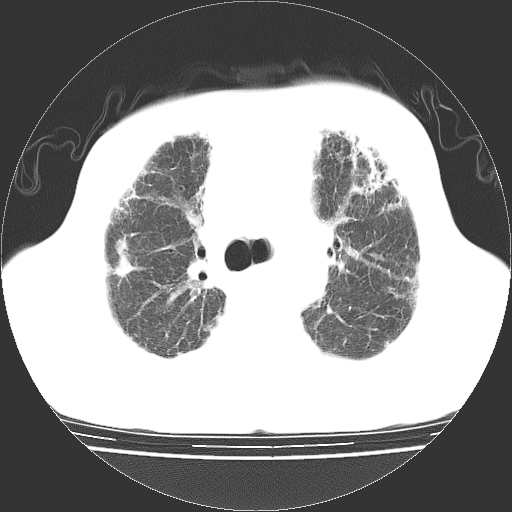

标题: CT25149:男,69岁,反复咳嗽、咳痰五年余,呼吸困难三天。 [打印本页]

男,69岁,反复咳嗽、咳痰五年余,呼吸困难三天。

慢支伴感染、肺气肿、肺心病

慢支伴感染、肺气肿、肺心病!支持!另:间质纤维化!

两肺间质性炎症并感染,左上叶肉芽肿

考虑慢性间质性肺炎并肺间质纤维化。

慢支伴感染、肺气肿、肺心病。双肺间质性改变(间质纤维化)。